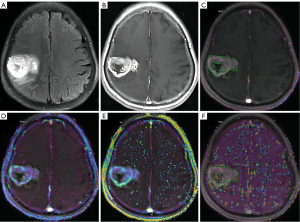

All DCE-MRI data were transmitted to a commercially available and clinically approved post-processing workstation (Sango via, Siemens Healthcare) for analysis using the Siemens Tissue 4D workflow according to the manufacturer’s instructions. Automatic motion correction and alignment were first performed. The tissue signal intensity was converted to gadolinium concentration. The two-compartment Toft’s model was used to fit the pharmacokinetic curves (17). Three types of the arterial input function (AIF; the slow, intermediate, and fast types), based on mathematical simulation, were automatically provided (18,19). According to the operation manual, one of the above three types with the smallest chi-square value was selected. ROIs were then sketched at the three consecutive and maximal levels of tumors after the consensus of two experienced radiologists according to previous studies (20-22). Within each level, two ROIs were positioned as follows:

- One ROI (irregularly shaped) encompassed all solid components of the tumor parenchyma (hereinafter referred to as the “tumor” region), excluding large vessels, meninges, and necrotic and hemorrhagic areas. ROI placements on DCE-derived maps were performed using T1CE as the reference when tumors showed enhancement; if there was no enhancement, T2-FLAIR images were used as the reference to draw the ROIs.

- The other ROI (circular, measuring 10 mm2) was randomly placed on areas extending ≤1 cm from the tumor margin (expressed as “peritumoral” hereinafter).

Representative images of the ROIs are shown in Figure 2. Thus, quantitative parameters, including Ktrans, Ve, and Kep, and the semiquantitative parameter iAUC which was in the first 60 seconds, were calculated. The minimum, mean, and maximum values of each DCE-MRI metric in each layer were recorded, and the average values of the three levels of each metric were used for analysis. A total of 24 parameters [2 ROIs (tumor parenchyma/peritumoral) × 4 parameters (Ktrans/Kep/Ve/iAUC) per ROI × 3 statistical values (the average of the maximum/minimum/mean values across the three levels) per parameter] were derived, such as the minimum value of Ve derived from the tumor parenchyma (tumor.Ve.min).